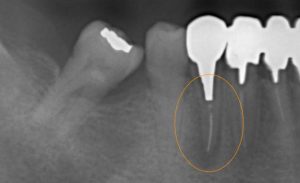

以前に他院にて根管治療を受けられた際に折れ込んだファイルが根管内にあります。

周囲の骨の中でその歯が原因の炎症が強くなり、歯肉が化膿により腫れ、噛むと痛むという自覚症状がでてきてしまったため根管治療を行うことにとなりました。

上下ともに当院初診時のレントゲンです。

下の写真は奥歯のブリッジ治療が終わり、ファイルの折れ込みや歯肉の腫れがある歯を治療するため銀歯とメタルコア(金属の芯)を除去したところです。